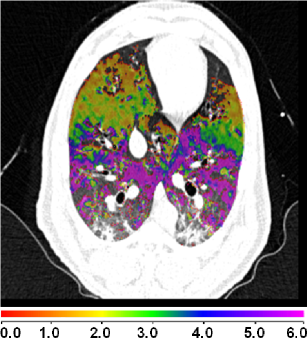

Figure 8(a) shows a comparison between the registration-derived indices of ventilation and the Xe-CT estimated sV in cube-shaped regions of interest for animal D. The corresponding Xe-CT regions in the are divided into about 100 cubes. Figure 8(b) is the Xe-CT estimate of sV. Figure 8(c), (d), (e) are the corresponding registration ventilation measures SAJ, SACJ and SAI. The regions with edema are excluded from the comparison. Figure 8(b) to (d) all show noticeable similar gradient in the ventral-dorsal direction. Notice that the color scales are different in each map and are set based on the range of values from the appropriate plot in Fig. 9.

Figure 9 shows scatter plots comparing the registration ventilation measures and the Xe-CT ventilation sV in all four animals. The SACJ column shows the strongest correlation with the sV (average ). The SAJ, which is directly related to Jacobian as , also shows good correlation with the sV (average ). The intensity-based measure SAI shows the lowest correlation with the sV (average ).